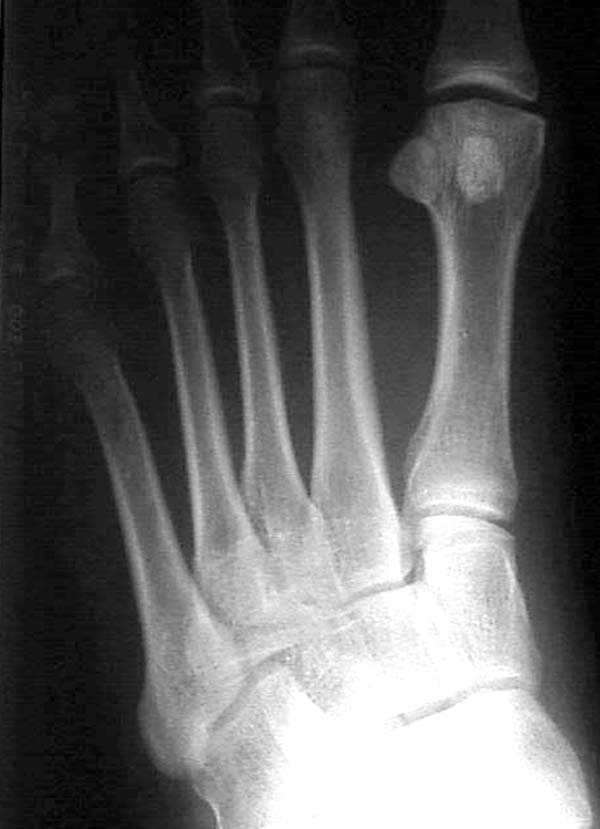

Здесь КТ и сравнительные снимки стопы под нагрузкой.

Диагностировано повреждение медиальной и латеральной колонны.